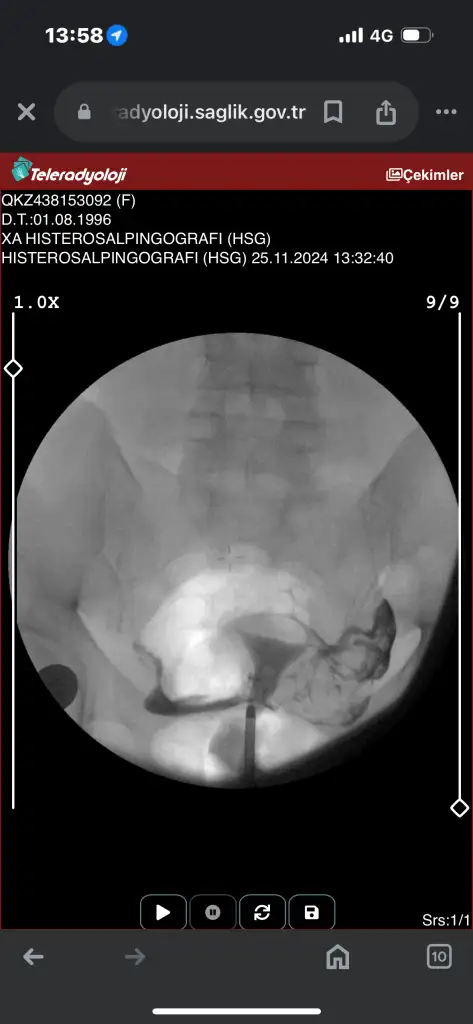

Canım tek tüpün kapalı galibaKızlar acil sonucuma bakarmısınızz ben hiçbirşey anlamıormm